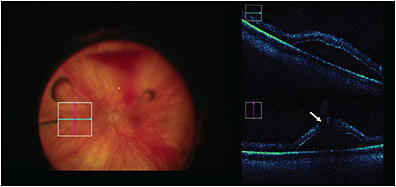

Optical coherence tomography (OCT) is a quick and noninvasive imaging modality capable of discerning high-resolution morphologic features of the retina and surrounding structures.1 Over the past 20 years, OCT has evolved to become an integral component of ophthalmic diagnosis, management, and therapeutic monitoring, with an estimated tens of millions of images captured per year.2 During this time, improvements in OCT technology have enabled the transition from an outpatient imaging modality to the operating room.

Integration of OCT into the operating room was initially limited by the bulky equipment and design of clinical systems that required patients to be cooperative and positioned upright. This hurdle was overcome through the development of the handheld OCT, introduced to the surgical suite in 2009, which allowed imaging of patients who were supine and under anesthesia.3 This system was further updated to a microscope-mounted OCT configuration, which served to ameliorate previous critical limitations in scan reproducibility and precision. The use of these microscope-mounted external intraoperative OCT (iOCT) systems enabled extensive study and clinical evaluation of iOCT during vitreoretinal surgery, including study of the potential positive impact on surgical decision-making, with key findings from the PIONEER study highlighting the potential role in confirming achievement of surgical objectives and guiding decisions regarding need for tamponade choice or restaining.4-6

However, it was not until the advent of microscope-integrated OCT systems that widespread utilization became feasible.7,8 Following their initial development, the next major milestone was the FDA clearance of the first microscope-integrated system,9 which provided broad availability of efficient, real-time visualization of surgical manipulations and the cross-sectional surgical anatomy.10-14 Current commercially available iOCT options include the Leica Envisu handheld system and Enfocus microscope-integrated system, the Zeiss Rescan 700, and the Haag-Streit Surgical iOCT system. This review will focus on recent advancements in iOCT technology and its current utility in retinal surgery.

There has been significant advancement from the conventional microscope-integrated systems that first made the commercialization and adaptation of iOCT to a wider audience possible.14-16 One key initial advance of iOCT was the injection of the OCT datastream into the microscope ocular that enabled simultaneous visualization of the surgical field and OCT imaging.13,15 Although a major innovative improvement, limitations to image quality and contrast with current systems have often resulted in the use of external monitors for OCT review.12,17